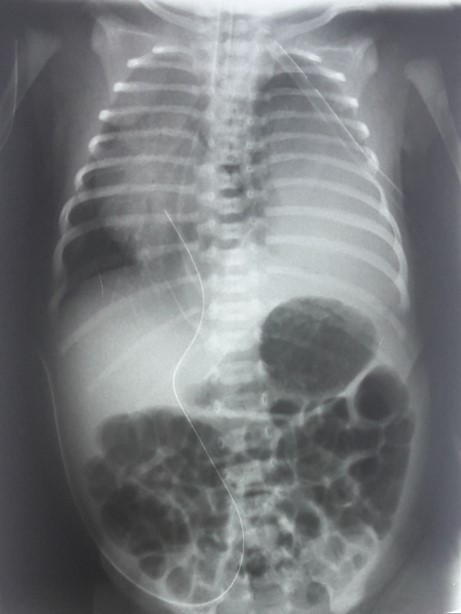

Se insertó tubo de drenaje torácico izquierdo liberando el neumotórax. Se realizó una radiografía torácica de control demostrando resolución del neumotórax, sin embargo, el desplazamiento contralateral del mediastino y corazón, persistían, además se observó una imagen radiopaca en la base del hemitórax izquierdo (Ver figura 1).

Figura 1. Radiografía de tórax

Se observa desplazamiento del corazón y estructuras mediastinales hacia el lado contralateral de donde se observa una imagen radiopaca en la base del hemitórax izquierdo.